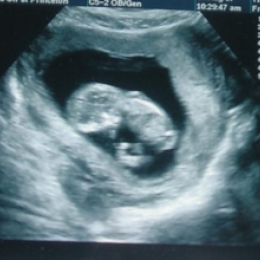

Как использовать данные УЗИ при беременности?

Установление беременности и оценка ее развития на ранних сроках - одна из главных задач УЗИ в акушерстве.

Сегодня УЗИ является единственным методом, позволяющим объективно наблюдать за развитием эмбриона с самых ранних этапов его развития. Использование эхографии в 1-ом триместре (1-12 недели) беременности дает более ценную информацию по сравнению с клиническими и гормональными методами исследования.

УЗИ - диагностика беременности возможна с самых ранних сроков (5-6 неделя от первого дня последней менструации). В отдельных случаях возможно выявление плодного яйца уже на 12-15-й день от момента зачатия.

Оценка жизнедеятельности эмбриона основывается на регистрации его сердечной деятельности и двигательной активности. В настоящее время можно осуществлять регистрацию сердечной деятельности эмбриона с 5 недель от момента зачатия. Двигательная активность эмбриона начинает выявляться при ультразвуковом исследовании с 8 недель беременности.